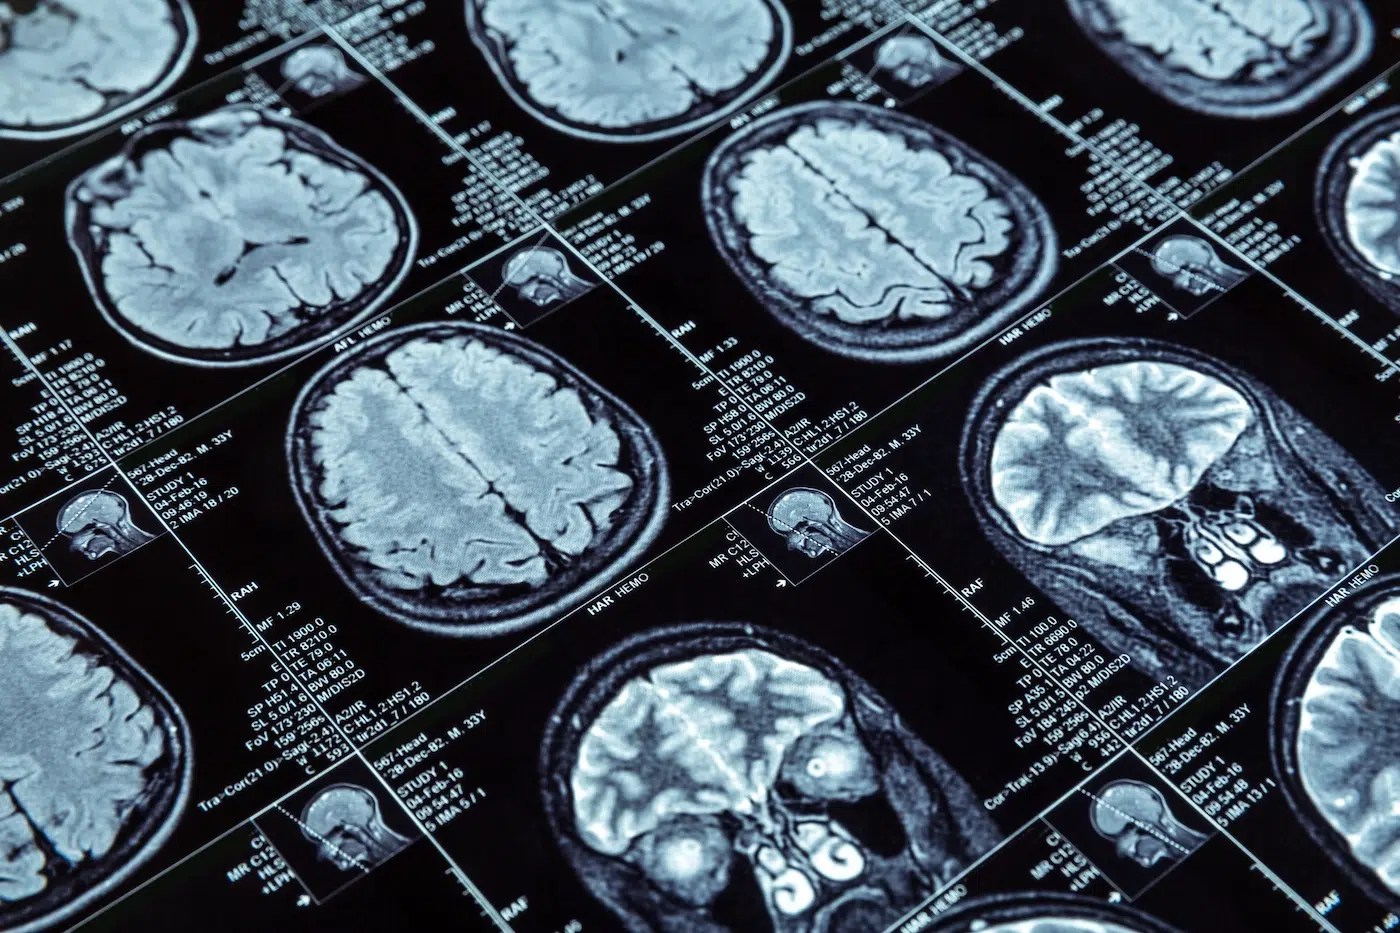

Memory loss following an accident is more than a temporary side effect of shock; it is often the primary clinical indicator of a Traumatic Brain Injury (TBI). Globally, an estimated 55 million people live with the lasting effects of a TBI, with more than 10 million new cases occurring every year. In the United States alone, these injuries contribute to over $75 billion in annual medical costs and lost productivity, underscoring the massive economic and personal scale of the problem.

Memory loss is a term describing any issue with creating or storing new memories or recalling existing ones. It occurs when the brain areas responsible for processing and organizing information are disrupted or damaged.

A person with memory loss may have problems with short-term memory, meaning they struggle to keep track of new information and recall it shortly afterward. They may also have challenges with long-term memory, which involves storing and later retrieving past experiences. The type and severity of these difficulties often depend on how and where the brain suffered damage.